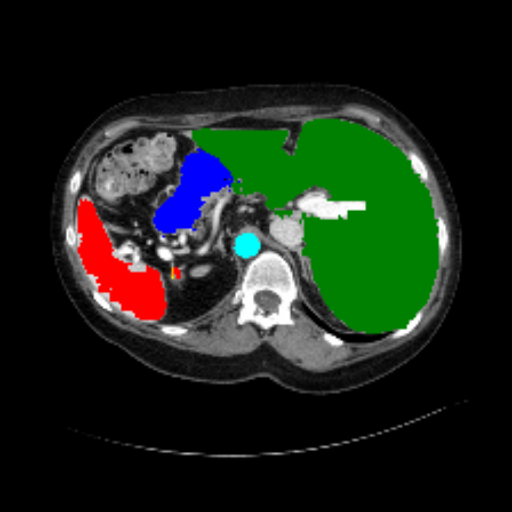

Figure 3 presents a qualitative comparison of segmentation performance on examples from the Synapse, BTCV, ACDC, and ISIC17 datasets. The first two examples (from Synapse) highlight variations in segmentation performance among U-Net, TransUnet, Mamba-Unet, and Swin-Unet. While Swin-Unet performs well in the first example, its performance decreases in the second example, particularly in segmenting the organ highlighted in blue. Additionally, it misclassifies background regions as the class highlighted in orange. In contrast, our approach demonstrates high robustness in segmenting all classes accurately and aligning well with the ground truth masks.

Across BTCV, ACDC, and ISIC17, the comparison methods exhibit varying performance depending on the task and class. For instance, Mamba-Unet struggles to segment multiple organs in BTCV, even misclassifying certain classes as others. In the ACDC dataset, both TransUnet and Mamba-Unet perform poorly in segmenting the three classes. In the last column (ISIC17), Swin-Unet oversegments the skin lesion compared to the ground truth. Unlike the comparison models, our approach consistently delivers effective segmentation across different tasks and datasets.

These qualitative findings further reinforce the quantitative results presented in the experimental section, demonstrating the effectiveness of our MambaCAFU model in handling binary and multi-class segmentation across diverse medical imaging modalities and tasks.

Slice GT Unet TransUnet Mamba-Unet Swin-UMamba MambaCAFU-V1

Figure 3: Visual comparison of segmentation examples from Synapse (first two examples), BTCV (3-4 examples), ACDC (5th example) and ISIC17 (last example). Columns: input slice, ground truth, Unet, TransUnet, Mamba-Unet, Swin-UMamba, and MambaCAFU-V1.